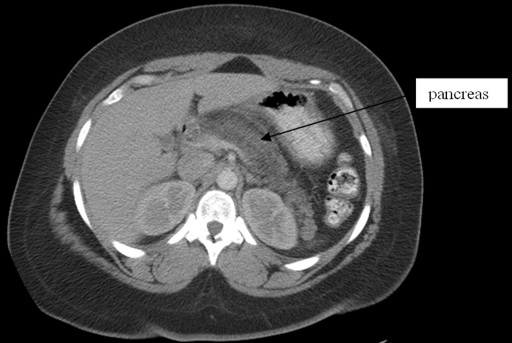

A 37-year-old African-American female was admitted with complaints of epigastric pain and emesis for one day. She denied any change in bowel habits, fever, cough or hematemesis; however she did admit to alcohol ingestion two days prior to admission. She related a history of moderate alcohol consumption and an episode of pancreatitis three years prior. There was epigastric tenderness on physical examination. Laboratory tests showed WBC 9,800 cells/mm3, normal liver enzymes (AST 22 U/L; ALT 16 U/L; alkaline phosphatase 55 U/L; total bilirubin 0.6 mg/dL), normal serum triglyceride level (54 mg/dL); amylase and lipase were 95 U/L and 31 U/L, respectively. CT scan of the abdomen with intravenous contrast showed swelling of the head and body of the pancreas with peripancreatic inflammatory changes consistent with acute pancreatitis (Figure 2). Abdominal ultrasound revealed a common bile duct diameter of 3 mm, no gallbladder wall thickening or gallstones. The patient was treated with intravenous fluids and analgesics. Amylase and lipase levels remained normal throughout the admission. Three days after admission, she was discharged home with complete resolution of symptoms.

Figure 2. CT scan of the abdomen with contrast (Case #2). |